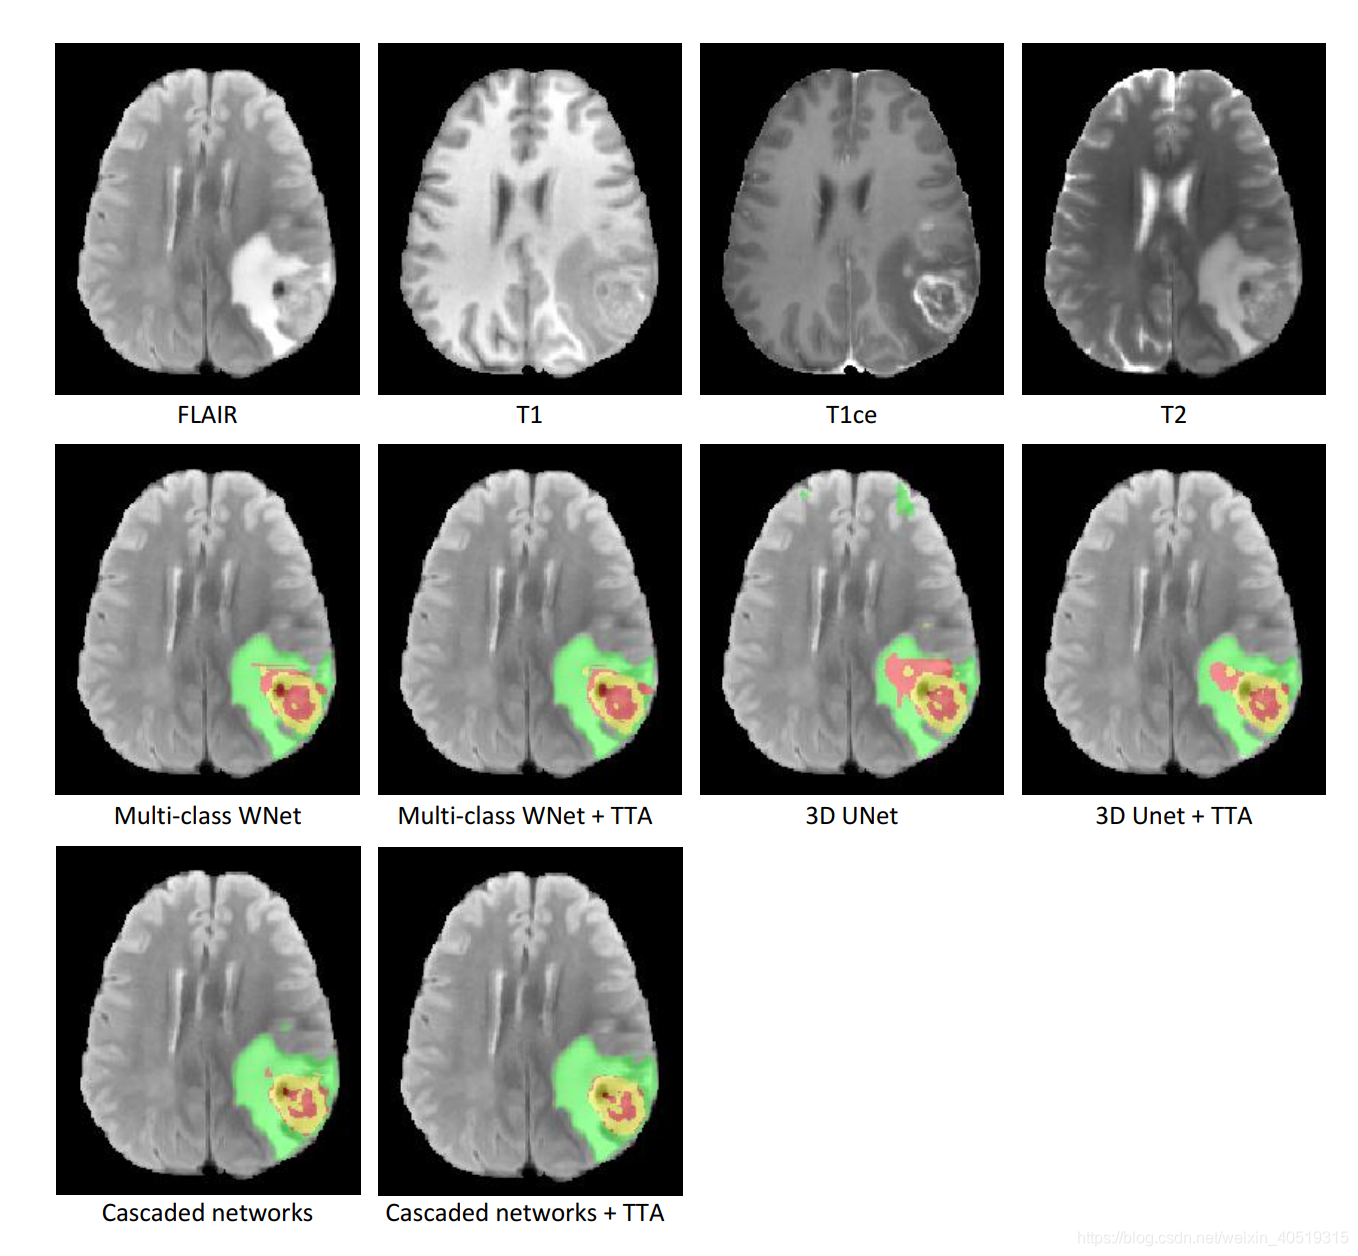

Fig. 1. An example of brain tumor segmentation results obtained by different networks and test-time augmentation (TTA). The first row shows the four modalities of the same patient. The second and third rows show segmentation results. Green: edema; Red: non-enhancing tumor core; Yellow: enhancing tumor core.

图1所示。一个例子的脑瘤分割结果获得不同的网络和(TTA)。第一行显示了同一病人的四种模式。第二行和第三行显示分割结果。绿色:水肿;红色:肿瘤核心无强化;黄色:增强肿瘤核心。

Segmentation Results. Fig. 1 shows an example from the BraTS 2018 validation set. The first row shows the input images of four modalities: FLAIR, T1, T1ce and T2. The second and third rows present the segmentation results of 3D UNet, multi-class WNet, cascaded networks and their corresponding results with test-time augmentation. It can be observed that the initial output of the 3D UNet seems to be noisy with some false positives of edema and non-enhancing tumor core. After using test-time augmentation, the result becomes more spatially consistent. The output of multi-class WNet also seems to be noisy for the non-enhancing tumor core. A smoother segmentation is obtained by multiclass WNet with test-time augmentation. For the cascaded networks, test-time augmentation also leads to visually better resutls of the tumor core.

分割结果。图1显示了来自BraTS 2018验证集的一个示例。第一行显示了四种模式的输入图像:FLAIR、T1、T1ce和T2。第二行和第三行分别展示了3D UNet、多类WNet、级联网络的分割结果以及相应的测试时间扩展结果。可以观察到3D UNet的初始输出似乎是有噪声的,存在水肿和肿瘤核无增强的假阳性。在使用测试时间扩展之后,结果在空间上变得更加一致。对于非增强的肿瘤核心,多类WNet的输出也有一定的噪声。通过增加测试时间的多类WNet可以获得更平滑的分割。对于级联网络,测试时间的延长也会带来更好的肿瘤核心的视觉恢复。